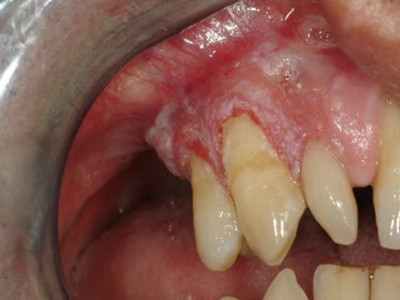

牙龈癌多源于牙间乳头及龈缘区,溃疡呈表浅、淡红,以后可出现增生。由于黏骨膜与牙槽突附着甚紧,较易早期侵犯牙槽突骨膜及骨质,进而出现牙松动,并可发生脱落。X线片可出现恶性肿瘤的破坏特征虫蚀状不规则吸收。

牙龈癌常发生继发感染,肿瘤伴以坏死组织,触之易出血。体积过大时可出现面部肿胀,浸润皮肤。

牙龈癌的发生可能与口腔卫生不良、不良修复体或义齿修复有一定关系;临床上有时亦见伴癌前病变存在;饮食习惯亦与牙龈癌发生有一定关系。多种致癌因素引起上皮细胞的基因突变,导致上皮异常增生,从而出现牙龈癌。